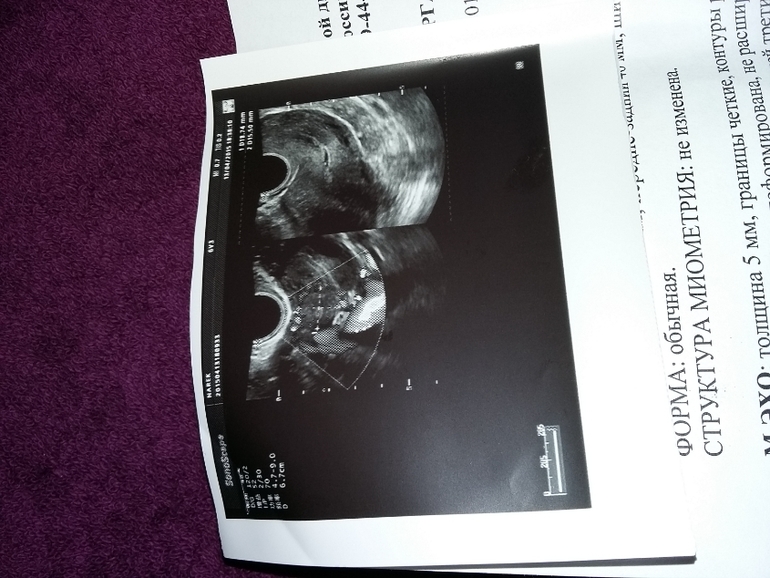

ФолликулометрияСходила на УЗИ, пол вечера проревела после. Может есть шанс что все будет хорошо в итоге. Посмотрите УЗИ. Предполагаемое зачатие могло быть 27 марта, или 4 апреля. Мазня три дня...((((фото далее...

матка маловата для беременности, эндометрий тонкийшансы что кто-то мог закрепиться в матке минимальны, плоду необходим эндик не меньше 8 мм.но бывают чудеса

Желтое тело маленькое у вас оч.для беременности...Обязательно надо ХГЧ и в динамике.

почему вы говорите, что маленькое? норма от 10 до 30 мм. у меня с двойней было 18 мм тело одно и второе 16 мм.. желтое тело вполне себе нормальное.

14 мм...У меня при ЗБ было 14 мм и врач сказала,что ЖТ оч маленькое...При внематочной было 16 мм...А при нормальной Б.21 мм.Для двойни не знаю какие нормы))Но ЖТ вырабатывает прогик,такой важный в самом начале и когда оно маленькое прогика не хватает...

у автора желтое тело 14 на 12, то есть вполне укладывается в рамки начальной стадии беременности. а замершая, маточная или эктопическая покажет время. в данном случае размер желтого тела ни о чем не говорит, что помогло бы разрешить загадку.

Спасибо. Меня аж трусит...ну хорошо что пошла, я планировала ОК начинать пить. Так как не планировали пока. Ну получилось так. А тепрь после УЗИ не знаю плакать или нет. Она сказала все не так. И форма плодного яйца, возможно срок маленький, но так как до 27 ничего не было, вполне возможно. И эндометрий тонкий...короче полную жопу.